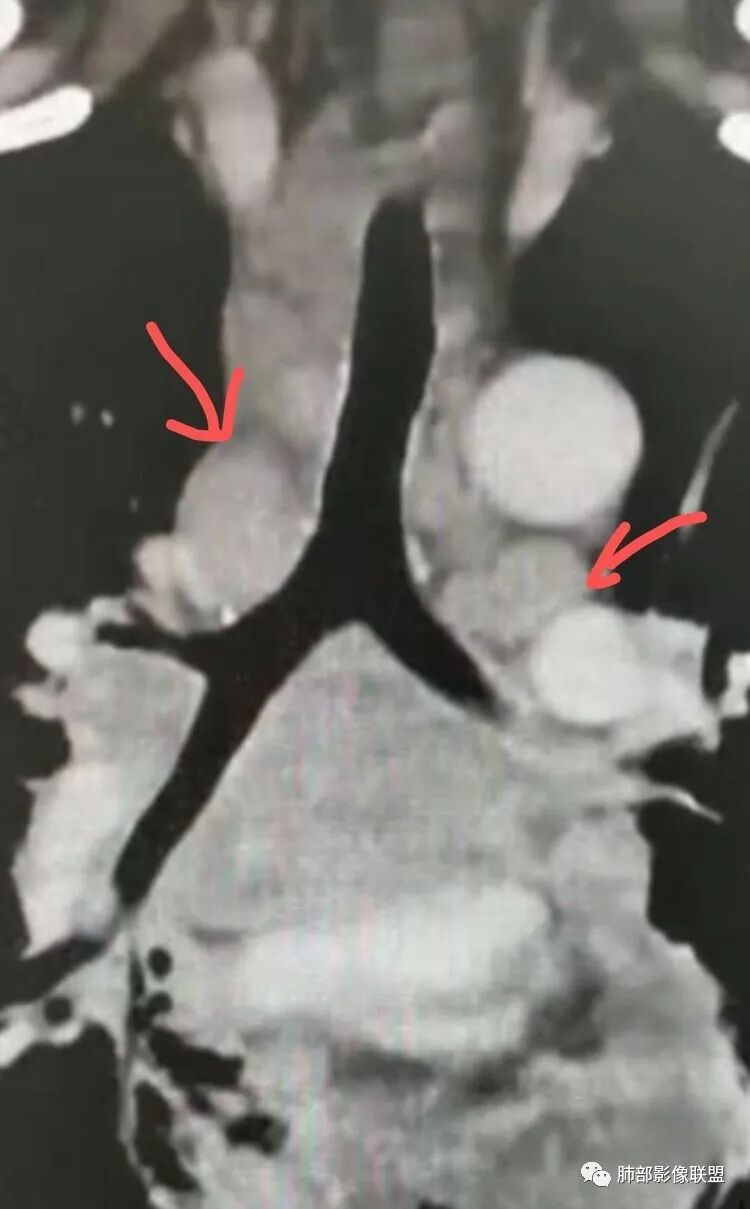

B超:腹膜后淋巴结肿大。胸部CT:纵隔、右肺门多发肿大淋巴结,部分融合呈团块状,纵隔淋巴结有坏死,右肺多发中轴间质增厚及小叶间隔增厚,部分实变,沿支气管血管束分布有多发粟粒结节影,右侧胸腔积液,心包积液。

TB…胸部淋巴结融合这么厉害,超声腹膜后的淋巴结,不知没融合的,有没有中央坏死特点

这些相对独立的,坏死都不明显

融合那些坏死支气管动脉漂浮

张三红:隆突小淋巴结坏死明显